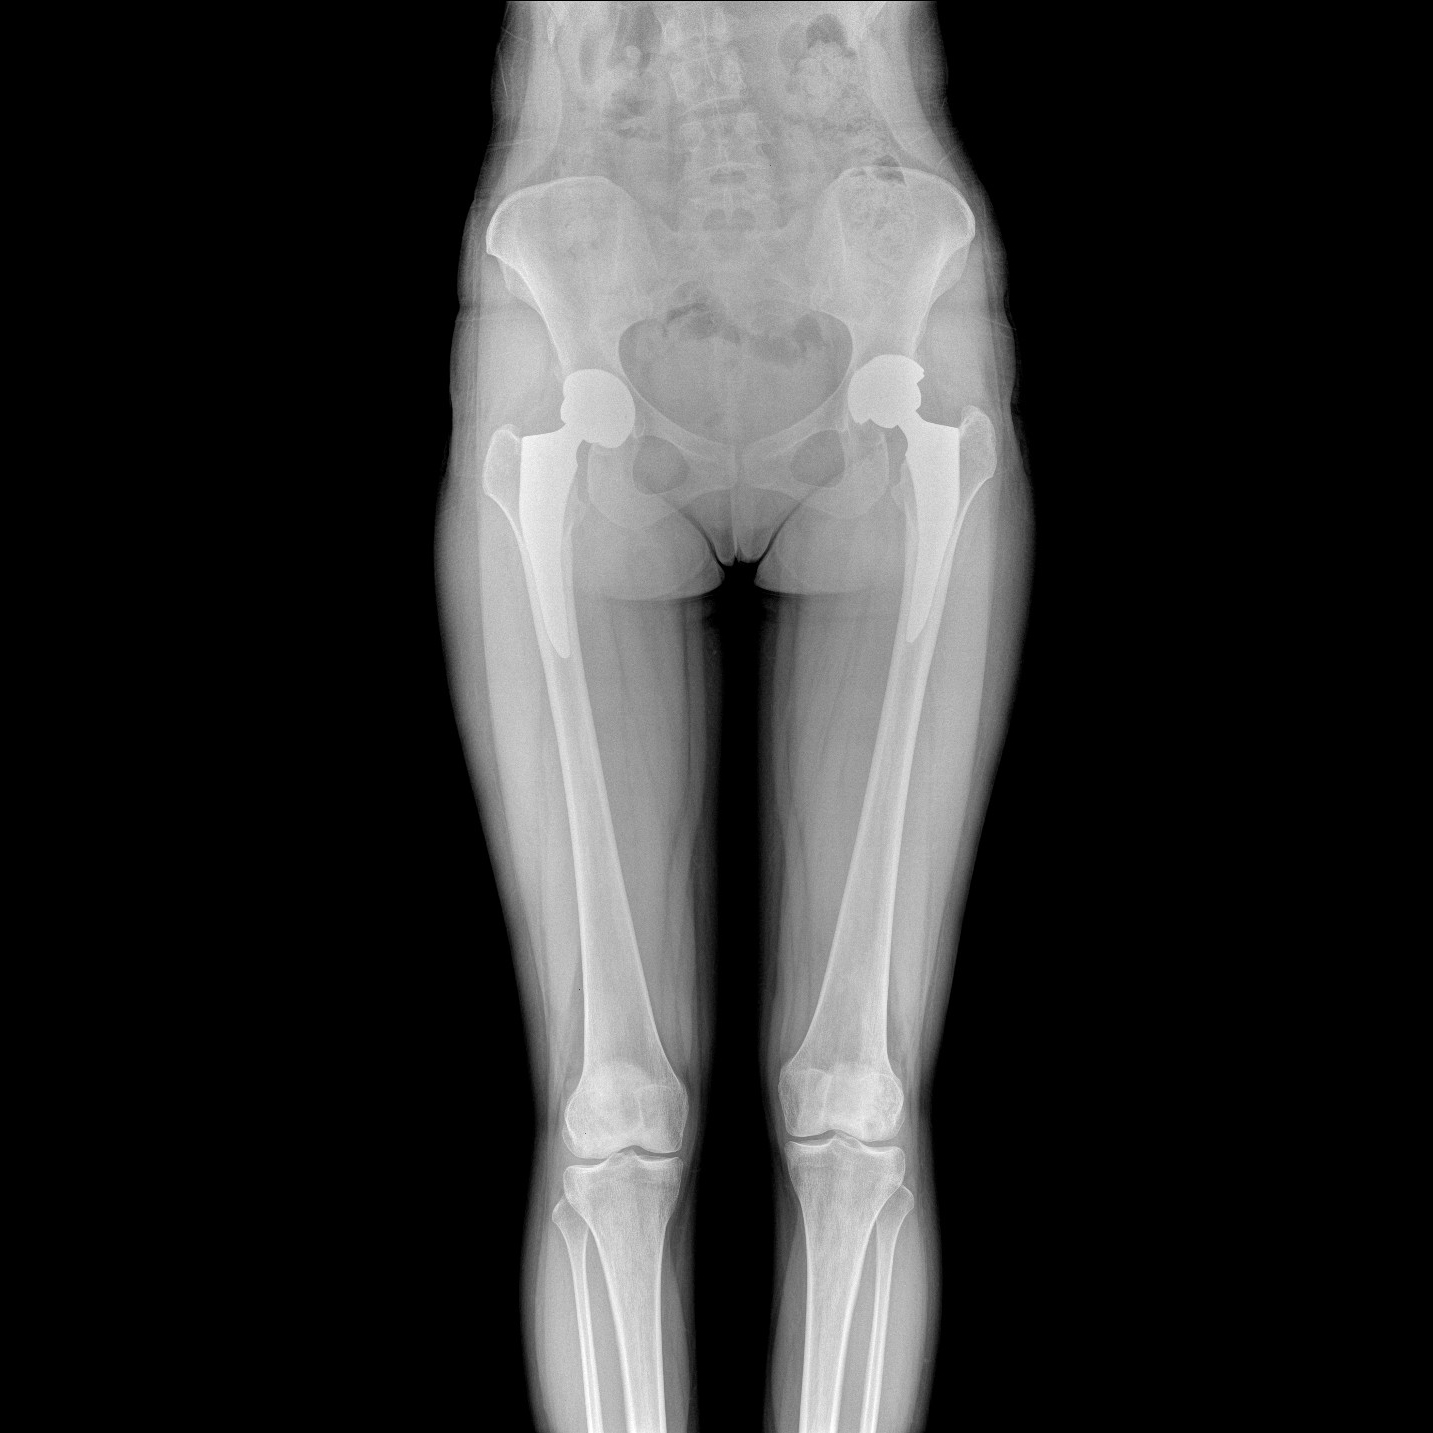

支持全脊柱攝影、雙下肢攝影、脊髓造影、復(fù)雜創(chuàng)傷、人工關(guān)節(jié)置換、關(guān)節(jié)損傷的修復(fù)重建等大視野臨床應(yīng)用

全脊柱一次成像 不拼接

17"*34"有效視野,一次成像不拼接。相較于多張攝影再軟件拼接的DR設(shè)備,PLX8600解決了拼接圖像存在密度不均勻,拼接處圖像配準(zhǔn)和放大效應(yīng)等問題,給臨床帶來了大視野影像解決方案,可一次性覆蓋全脊柱或雙下肢影像。

Clinical picture

臨床圖片